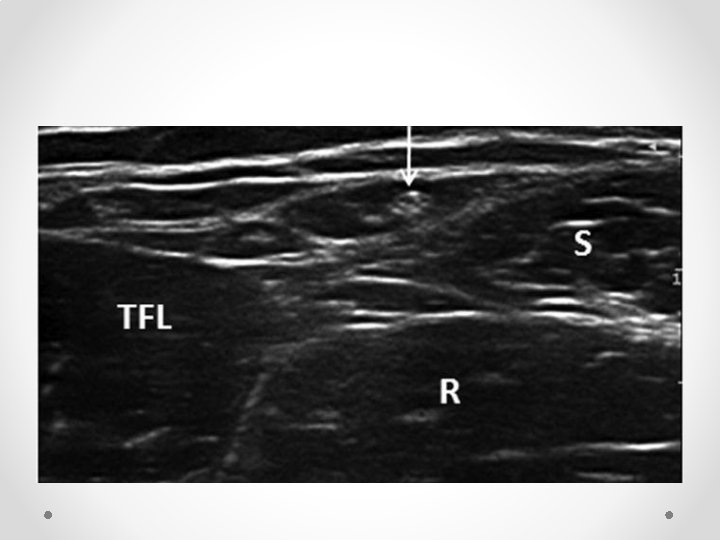

Ultrasound skills: • US blocks are composed of 2 skills o Identifying the nerves o Manipulating the needle • Identifying nerves: o KNOW YOUR ANATOMY o Practice scanning yourself o Nerves frequently run with arteries – look for an artery and nerve if often nearby- eg ilioinguinal, adductor canal, SSNB, popliteal tibial. o Nerves also tend to run in fascial planes – if you get your LA into the right plane it will usually work o Proximal nerves are mostly “nerve” (=fat=black) with little white connective tissue. As you move distally and branches are given off, nerves become a more speckled white colour due to higher proportion of connective tissue. Proximal nerves are more vulnerable to injury than distal nerves and blocks are associated with a higher risk of nerve injury o If unsure what you see is a nerve, scan proximally and distally- nerves will stay present, tendons and other things will tend to get bigger/ smaller/ disappear o If still unsure, stimulate the nerve eg 50 hz with RF needle (note RF needles can be very hard to see with US, especially for deep blocks

Left: (Proximal) brachial plexus (interscalene). Lots of dark nerve, little connective tissue Right: (Distal) - Median nerve (M) in forearm. Little nerve, lots of white connective tissue